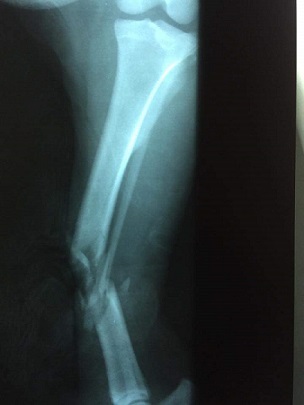

Heres your baby Chanders Mom

(IMG_2872.JPG)

(part0.jpg)

(part0 (1).jpg)

(part0 (2).jpg)

She was a little too rambunctious earlier---wanted to chase Luca across the hardwood floor when it was time to go out to pee. . . She's never off leash but she was spinning wheels trying to get Luc!!!! Lord she doesn't realize how much that dang back leg is worth now